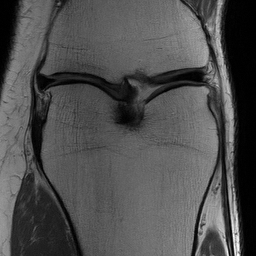

Refer to caption

Fig. 1: Foreground-to-Background Boundary Transistion Artifacts during patchwise inference. These artifacts are seen on the left edge of the image in the case of zero-padding (left) while being absent for reflection padding (right).

The usage of a single diverse prior trained on a large dataset with multiple anatomical regions transitions our prior, ϕ(x)\phi(x), away from a consistent idea of location. The proximal solution in image restoration techniques such as DiffPIR or DPS struggles particularly when foreground transitions to background, leading to horizontal or vertical lines as artifacts near generated image boundaries. This is accentuated in subsequent steps by the denoising prior. However, zero-padding is a standard part of shifted grid inference (Section 2.2) and necessarily generates such foreground-background transitions. One simple solution to avoid such artifacts is to simply avoid boundary discontinuities by switching to reflection-padding. This results in images free of transition artifacts as illustrated in Fig. 1.